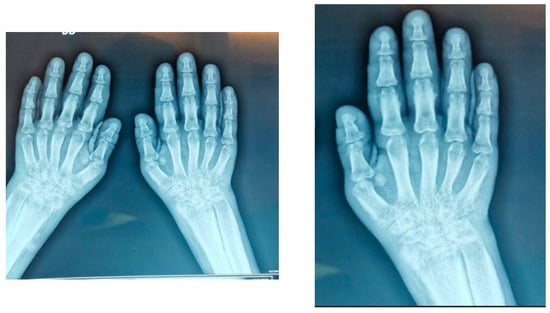

- Hand X-rays: bilateral carpitis with cortical thickening (Figure 3)